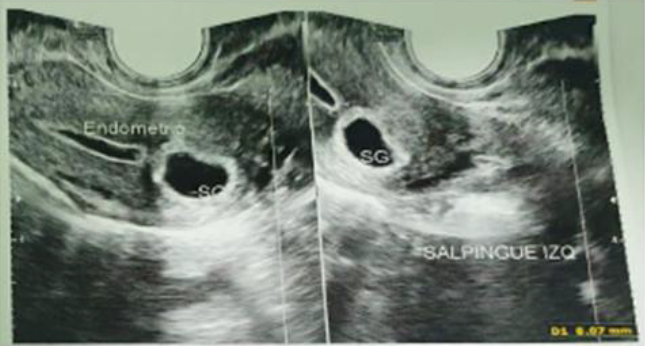

Evaluating ultrasonographic and diagnostic lapa-roscopy findings and perioperative complications in women with chronic pelvic pain at two tertiary hospitals in Zimbabwe: A cross-sectional study

DOI: 10.36205/trocar7.2026000